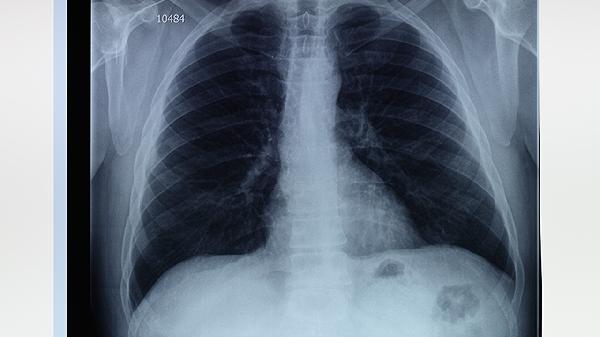

肺大泡通常由长期吸烟、慢性支气管炎或肺气肿等疾病导致肺泡壁破坏融合形成,主要表现为胸闷、活动后气短,偶有咳嗽但无咯血等典型肿瘤症状。影像学检查可见薄壁透亮区,边缘光滑无分叶或毛刺。肺癌早期多表现为孤立性结节或肿块,伴随痰中带血、消瘦等全身症状,CT可见病灶边缘不规则或有血管集束征。

极少数情况下,肺大泡周围可能因长期炎症刺激发生癌变,但概率极低。若肺大泡患者短期内出现症状加重、病灶增大或实变,需警惕合并肿瘤可能,此时需通过穿刺活检或PET-CT进一步鉴别。